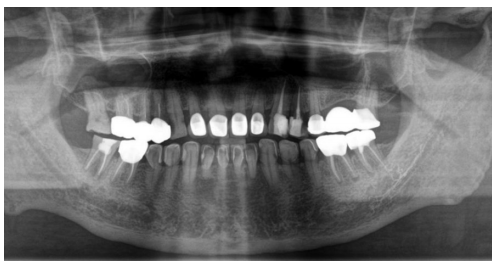

初诊时带来的5年前曲面体层片,如下图。

可见37冠部修复,根管内有高密度充填物影像,远中根管充填物沿伸至根尖周并进入左下颌管内,下颌管内有条状高密度影(近中至36远中根下颌管处,远中至下颌升支1/3处);初诊锥形束CT(CBCT)显示37根管内见高密度充填物影像,根尖周未见密度减低影,疑似大量充填糊剂沿37远中根进入下颌管内,并包绕于管壁。较5年前曲面体层片无明显变化。